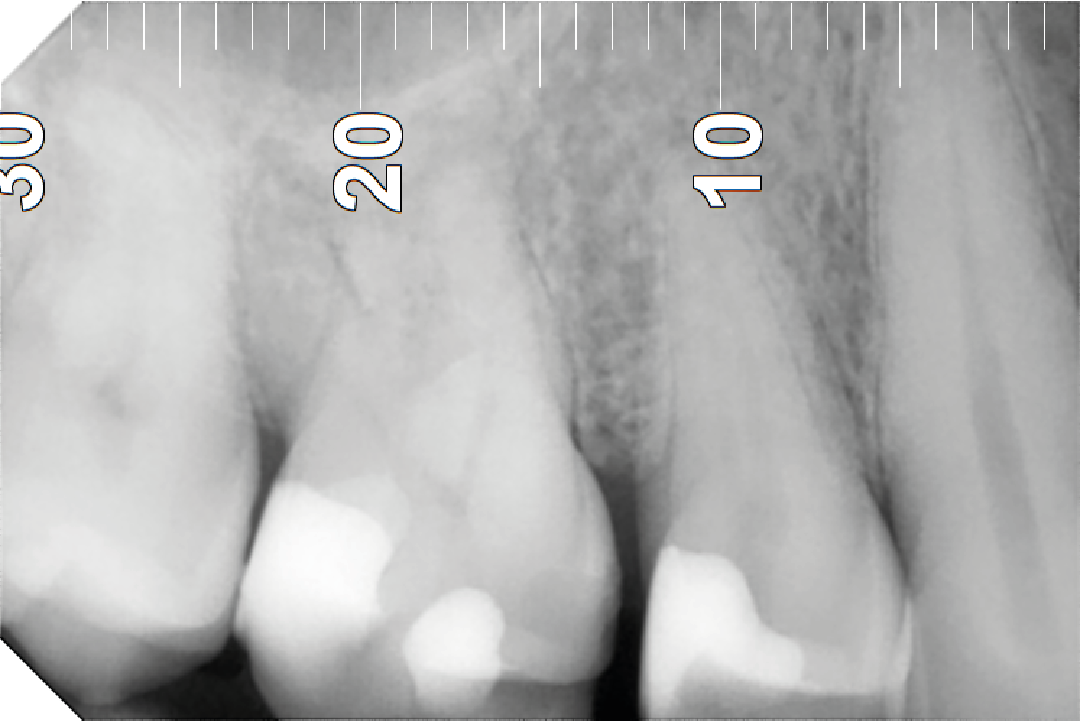

-NADA, puede que no haya dolor ni nada a simple vista pero en un examen radiográfico vemos

el origen del problema